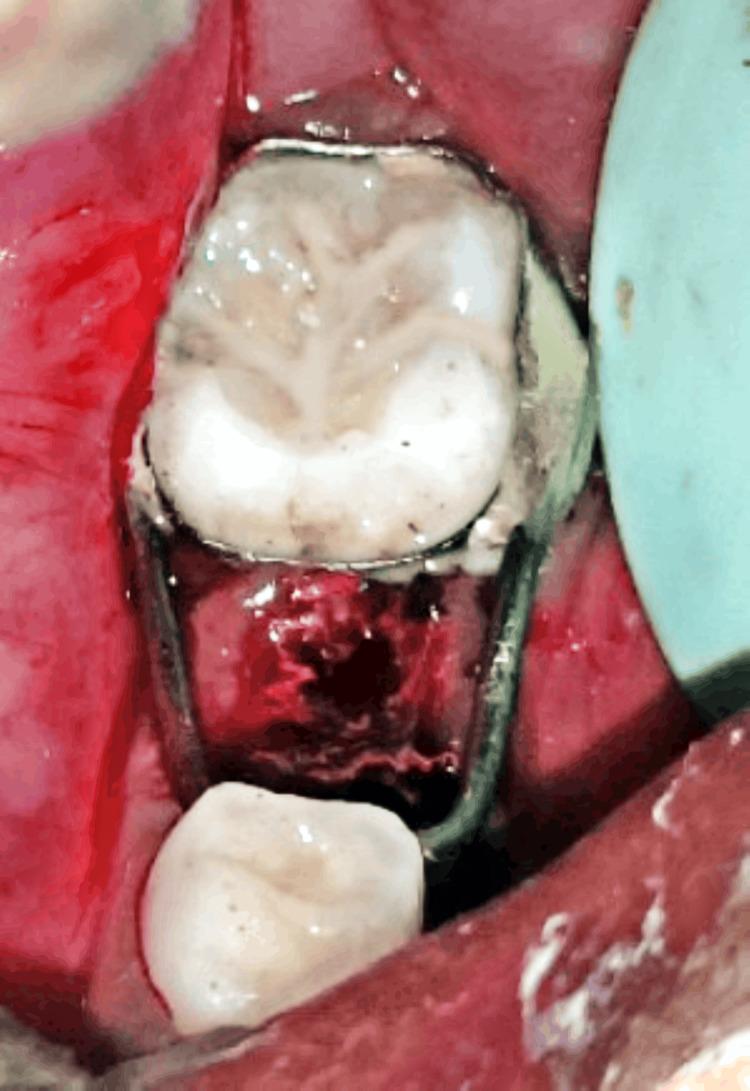

Oral health is a vital part of overall health, particularly for children with special healthcare requirements. The terms "dumb" and "mute" are frequently linked with the term "deaf" due to the connection between hearing loss and speech impairment. A hearing and speech-impaired child may be unable to express completely because of the communication barriers. It is important to treat special children with utmost care and safety. This case report describes the dental management of an 8-year-old special child reported with multiple carious lesions under general anesthesia as she was not well acquainted with sign language. In a hospital setting under general anesthesia (GA), all necessary treatments are carried out in a single appointment. Since it is monitored by a multi-disciplinary team it can safely provide effective care to a child with hearing impairment and mutism.

口腔健康是整体健康的重要组成部分,对于有特殊医疗需求的儿童尤为如此。由于听力丧失与言语障碍之间的关联,“哑巴”和“缄默”这两个词经常与“聋”这个词联系在一起。有听力和言语障碍的儿童可能由于沟通障碍而无法完全表达自己。以最大程度的关怀和安全对待特殊儿童非常重要。本病例报告描述了一名8岁特殊儿童的牙科治疗情况,该儿童因不太熟悉手语而在全身麻醉下被报告有多处龋损。在医院的全身麻醉(GA)环境下,所有必要的治疗都在一次就诊中完成。由于有一个多学科团队进行监测,它可以安全地为有听力障碍和缄默症的儿童提供有效的护理。